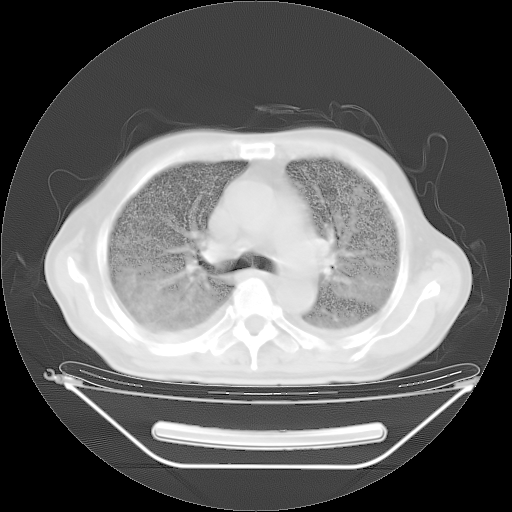

今天复查肺部CT,发现双肺广泛磨玻璃样改变。所以我把3月19日和5月9日相隔50天的肺部CT上传。请大家会诊。

5月9日肺部CT(在4月27日齐鲁医院肺部CT描述部分肺组织磨玻璃样改变,12天后肺组织广泛磨玻璃样改变)

2009年5月9日肺部CT